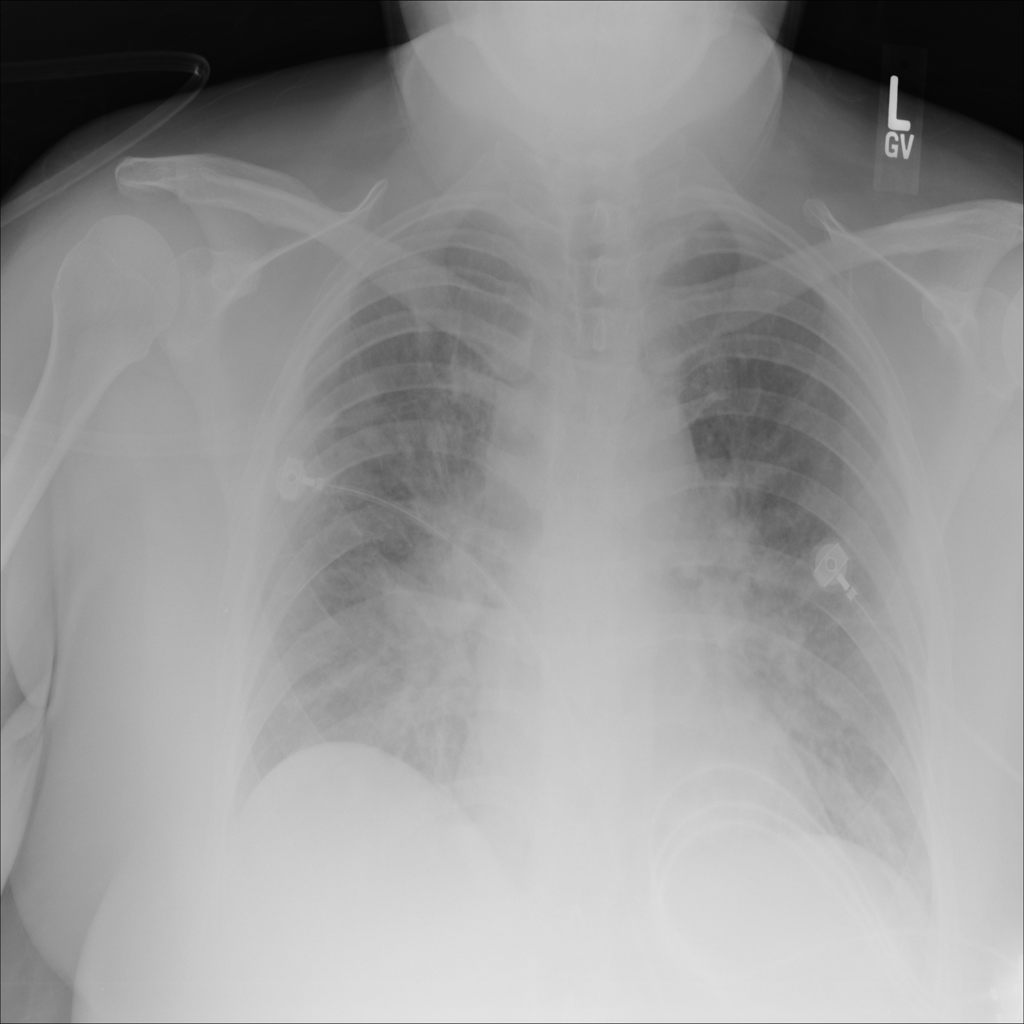

PAT-24D9 · IMG-006Edema

PAT-24D9 · IMG-006

AP